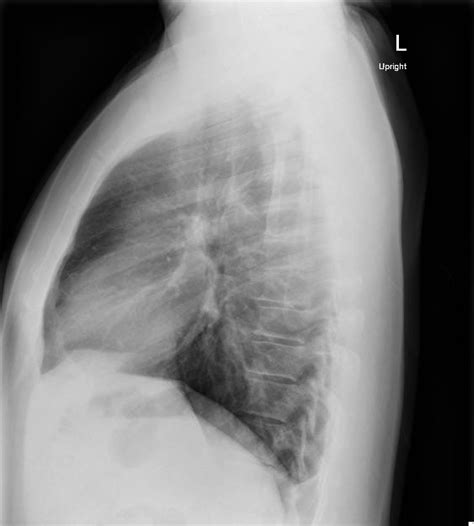

2. Positioning: The patient stands in front of the X-ray machine. For the lateral view, the patient is positioned sideways, with one side of the chest facing the X-ray plate.

3. Exposure: The radiographer will instruct the patient to hold still and may ask them to take a deep breath and hold it. This helps to expand the lungs and provide a clearer image.

4. Image Capture: The X-ray machine emits a small amount of radiation, which passes through the body and creates an image on the X-ray plate. The process is painless and quick.